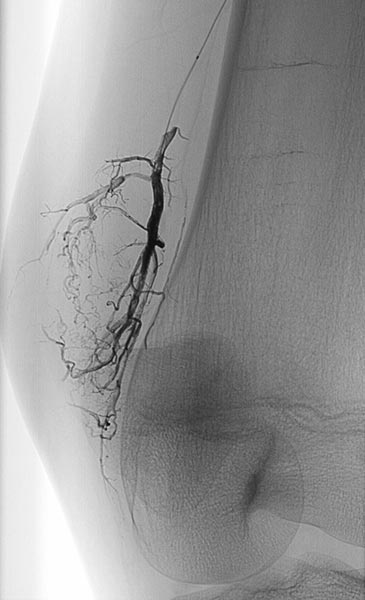

Die digitale Subtraktionsangiographie (DSA) in der früharteriellen Phase zeigt eine, aufgrund der chronischen Mehrdurchblutung erweiterte, zuführende Arterie (sogenannte Feederarterie), in diesem Fall eine Arteria genu superior medialis.

Die digitale Subtraktionsangiographie (DSA) in der arteriellen Phase 2 s später zeigt einige kleinere arteriovenöse Fisteln.

Die digitale Subtraktionsangiographie (DSA) in der arteriellen Phase zeigt im Gegensatz zu einer arteriovenösen Malformation nochmals 4 s später keinen direkten frühvenösen Abstrom des Kontrastmittels, sondern eher ein Pooling-Phänomen.

Superselektive Sondierung der Arterie mit einem Mikrokatheter zeigt wiederum die multiplen, feinen arteriovenösen Fisteln, jedoch nicht den für eine AVM typischen sofortigen venösen Abstrom. Diese starken arteriovenösen Fisteln in die VM sind ungewöhnlich ausgeprägt.